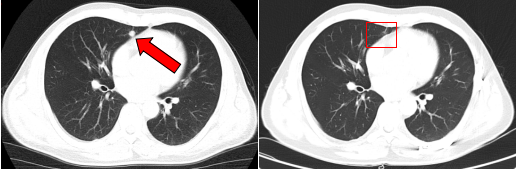

治疗前后鼻咽部病灶、咽后淋巴结病灶对比( 左:治疗前,右:治疗后)

2018年2月,复查MRI提示颈部淋巴结复发,患者在我院接受了淋巴结清扫术;2020年1月,胸部CT提示肿瘤转移至双肺,病情出现进展。医疗团队启用“晚期肿瘤布拉格治疗”方案,这一创新疗法融合了精准的局部放射治疗、GM-CSF刺激骨髓抗原释放技术,并联合免疫治疗,三管齐下。在完成14个周期治疗后,肺转移灶的代谢活性显著降低。